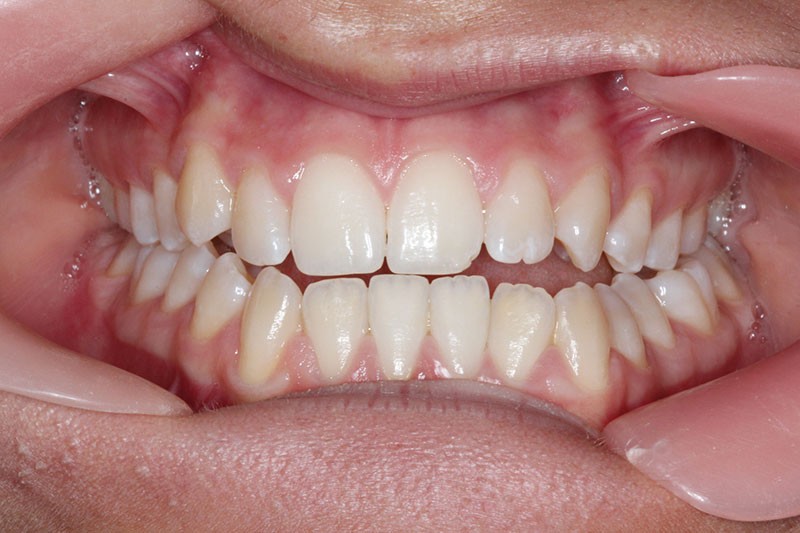

Nous sommes en présence d’une patiente en fin de croissance faciale, âgée de 16 ans. Elle présente une classe III dentaire et squelettique associée à une asymétrie faciale de type latérognathie mandibulaire avec déviation des points interincisifs et déviation du menton vers la gauche.

Pour des raisons personnelles, la patiente refuse un protocole orthodontico-chirurgical. Nous optons pour une réduction de la classe III par compensations dento-alvéolaires car la progénie n’est pas très importante et nous estimons que le résultat dentaire, squelettique et facial peut être cohérent. Un système « Motion Classe III Carriere » va être utilisé suivi d’un appareillage multibague « Carriere SLX ».